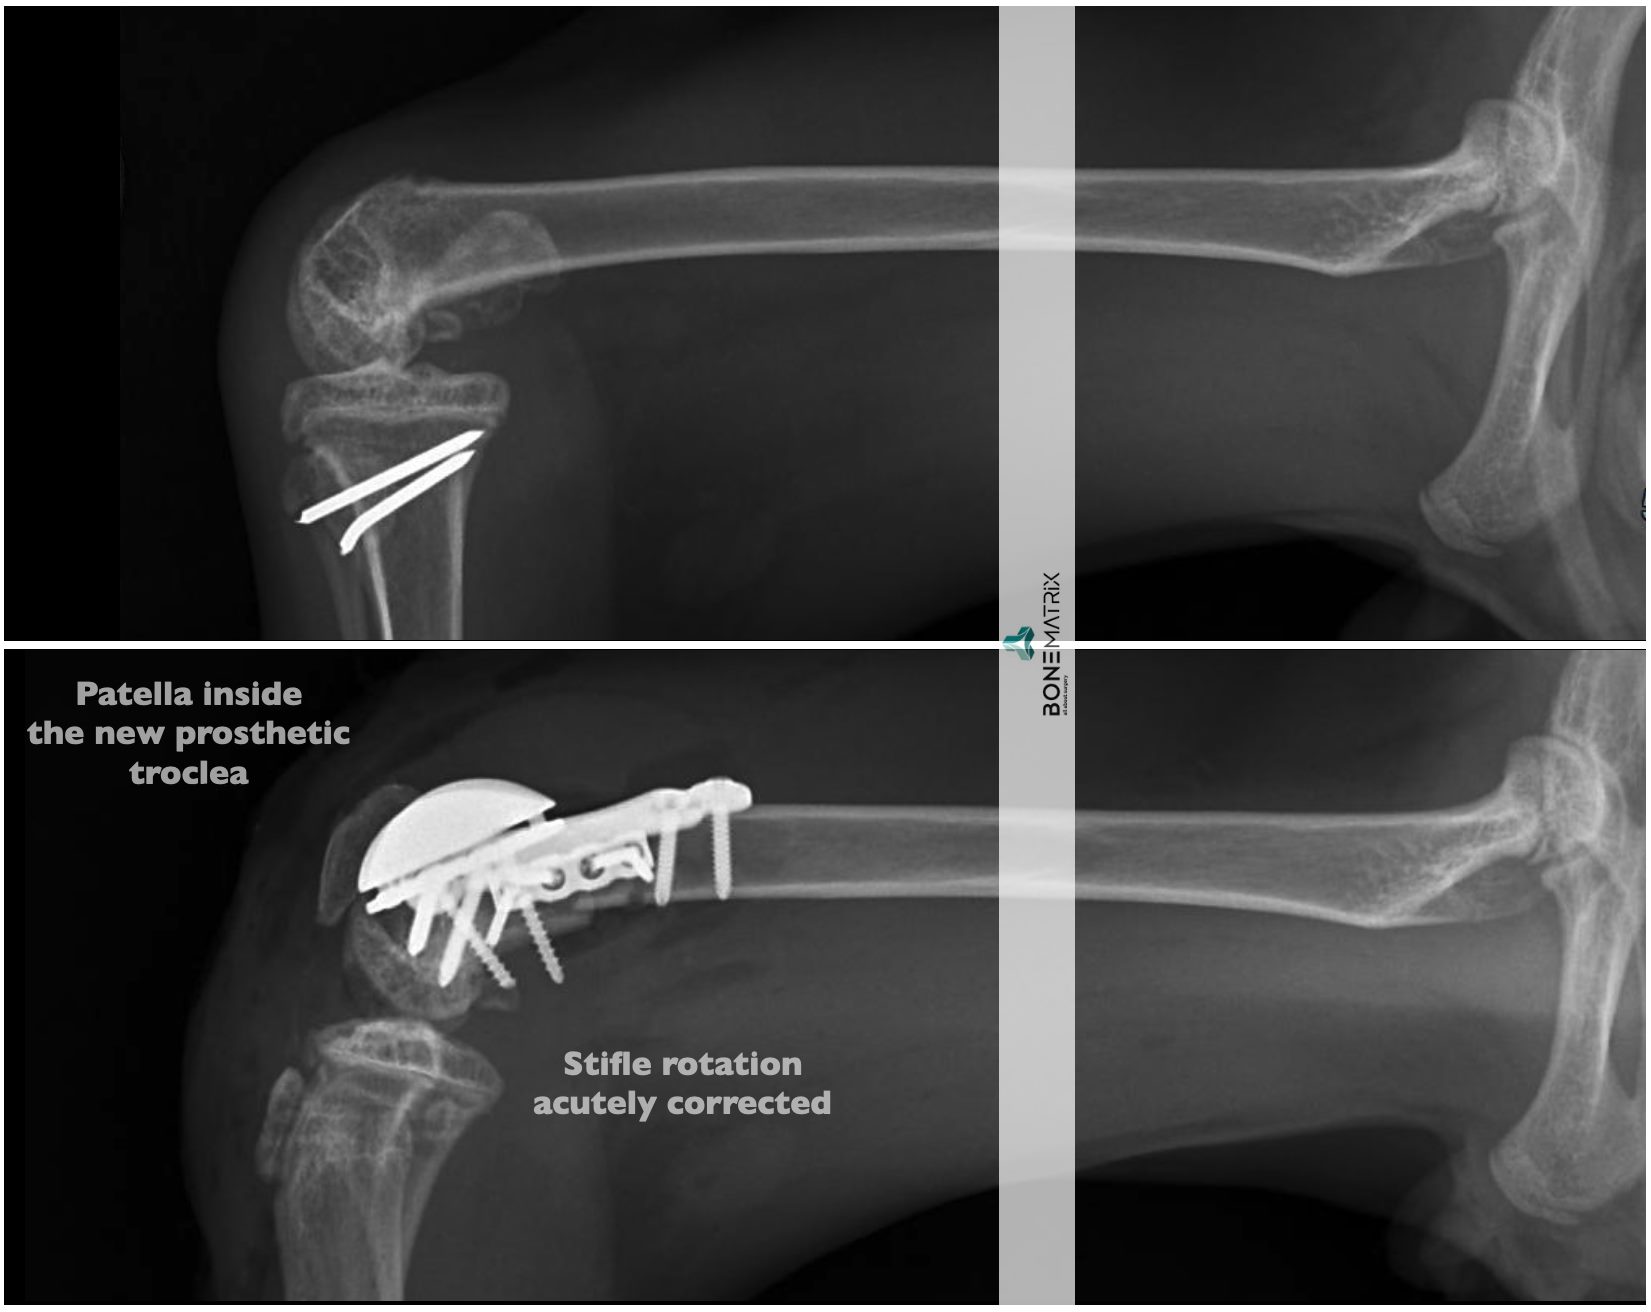

- rotação extrema do joelho

A imobilização de um membro supostamente para proteger uma reparação cirúrgica efetuada resultou em lesões muito mais graves que a inicial, comprometendo o membro de forma irreversível.

Num cenário de mais que provável amputação, acabamos por ter a sorte de encontrar tutores motivados que quiseram lutar por este membro. Uma cirurgia complexa reparou o que era possível, e um excelente trabalho de reabilitação devolveu a função possível a um membro perdido.